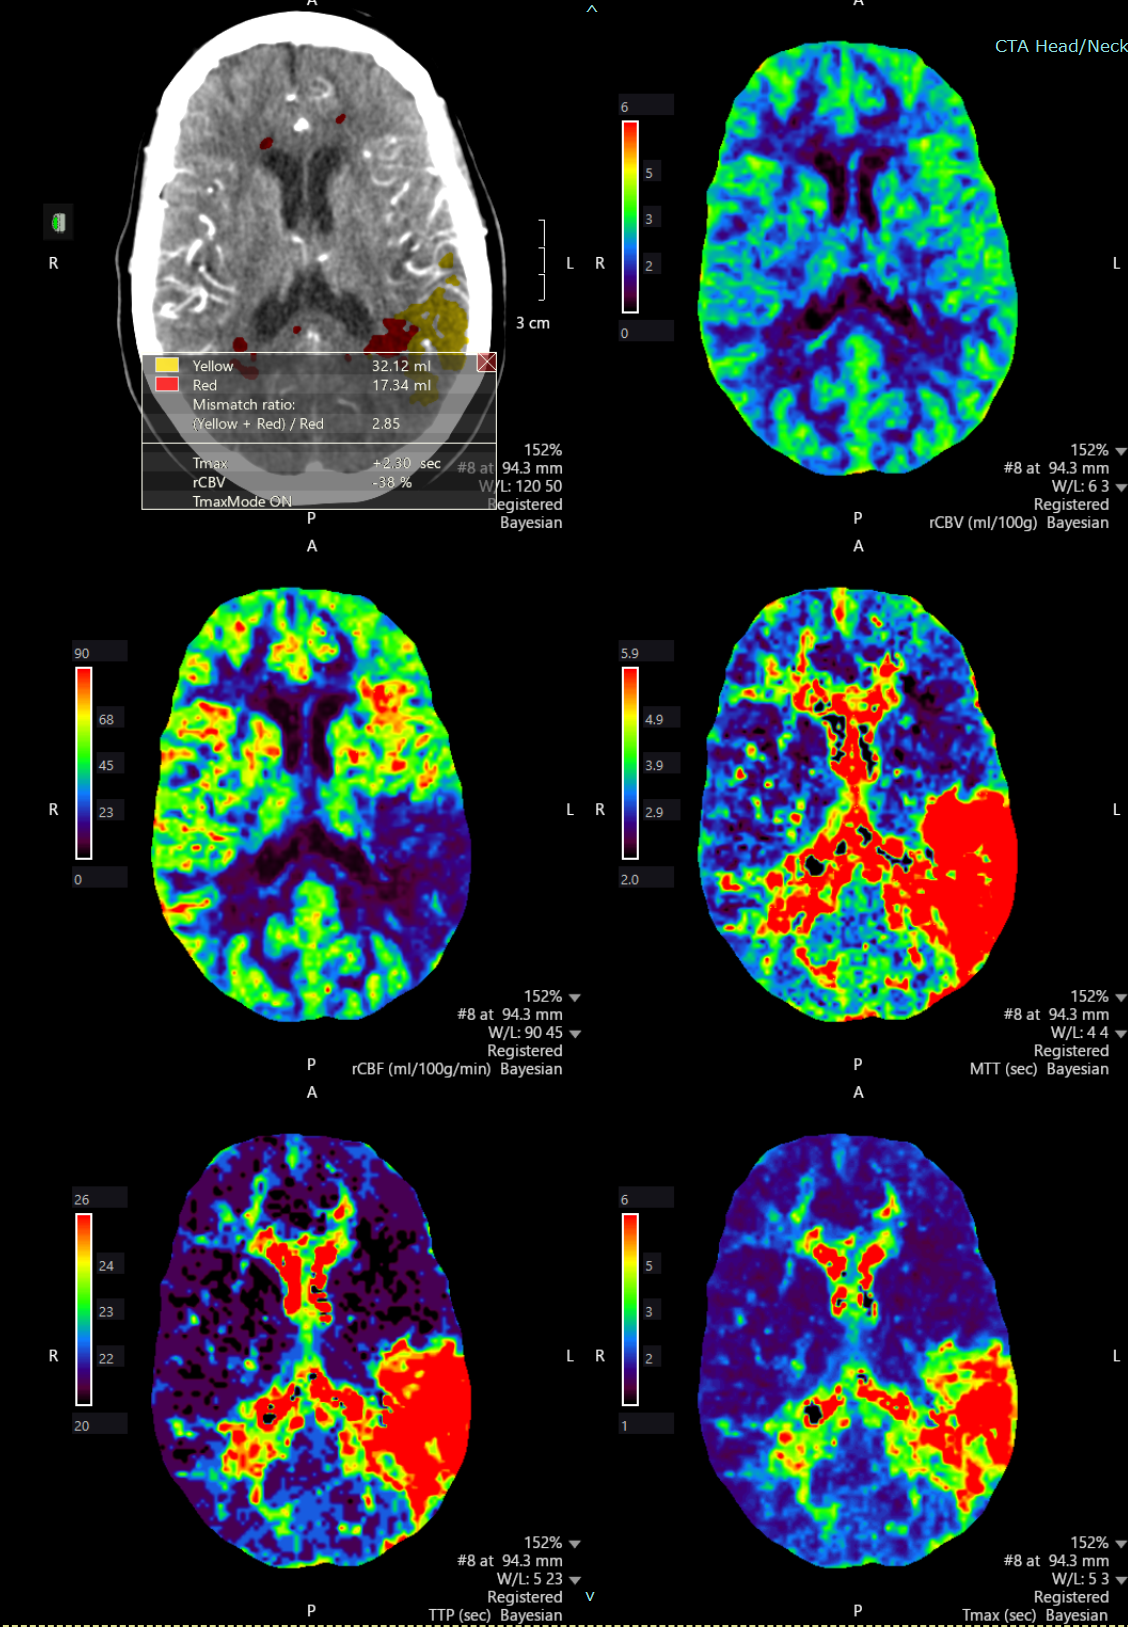

Perfusion images

1.4 mb

PNG